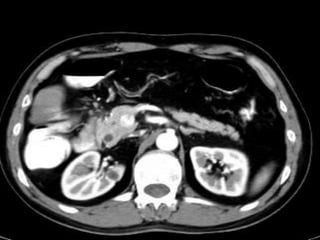

61 years old man with epigastric pain and vomiting

young patients (20–40 y), F : M  CT angiograms:            focal narrowing in the proximal celiac axis.             inspiration and expiration          2ry signs poststenotic dilatation and collaterals.ttt   : surgery.

angulations and narrowing of the proximal celiac axis. Sagittal 3D image of a patient with epigastric pain